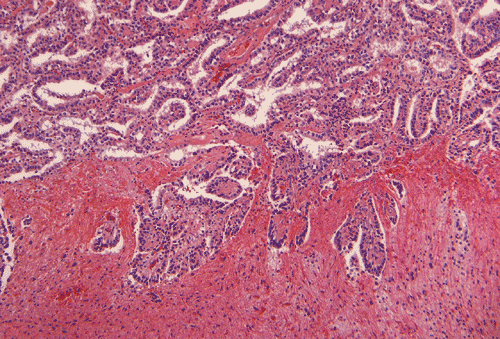

Intraoperative frozen section (Panel E) show an epithelial neoplasm with the tumor cells arranging in a single layered architecture. There is no necrosis present. The nuclear and cytoplasmic features are in general agreement with the cytologic preparation except that there is a mild degree of nuclear pleomorphism  (Panel F).

Permanent sections show a papillary epithelial neoplasm with invasion into the brain parenchyma (Panel G, H, and I ). In all areas the tumor cells maintained a single layered architecture. While a papillary structure is present in some area, the tumor cells arrange in a back-to-back cystic architecture intervened by a thin layer of fibrovascular stroma (Panel J). The nuclei are rather bland and monotonous. Mitotic figures are not readily seen  (Panel K). On immunohistochemistry, practically all tumor cells strongly express S100 protein (Panel L) and vimentin (Panel M). Most tumor cells are positive for cytokeratin (AE1/AE3) (Panel N). GFAP is expressed by some tumor cells (Panel O). The Ki-67 labeling index is about 1-2% (Panel P).